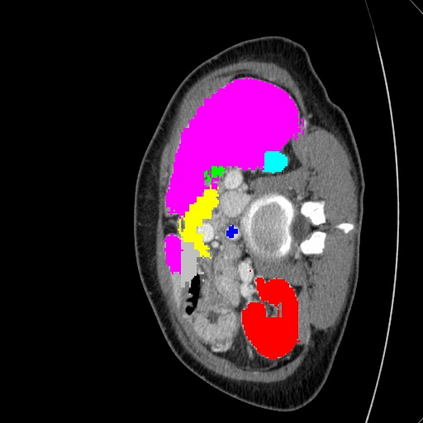

Transformers have made remarkable progress towards modeling long-range dependencies within the medical image analysis domain. However, current transformer-based models suffer from several disadvantages: (1) existing methods fail to capture the important features of the images due to the naive tokenization scheme; (2) the models suffer from information loss because they only consider single-scale feature representations; and (3) the segmentation label maps generated by the models are not accurate enough without considering rich semantic contexts and anatomical textures. In this work, we present CASTformer, a novel type of generative adversarial transformers, for 2D medical image segmentation. First, we take advantage of the pyramid structure to construct multi-scale representations and handle multi-scale variations. We then design a novel class-aware transformer module to better learn the discriminative regions of objects with semantic structures. Lastly, we utilize an adversarial training strategy that boosts segmentation accuracy and correspondingly allows a transformer-based discriminator to capture high-level semantically correlated contents and low-level anatomical features. Our experiments demonstrate that CASTformer dramatically outperforms previous state-of-the-art transformer-based approaches on three benchmarks, obtaining 2.54%-5.88% absolute improvements in Dice over previous models. Further qualitative experiments provide a more detailed picture of the model's inner workings, shed light on the challenges in improved transparency, and demonstrate that transfer learning can greatly improve performance and reduce the size of medical image datasets in training, making CASTformer a strong starting point for downstream medical image analysis tasks.